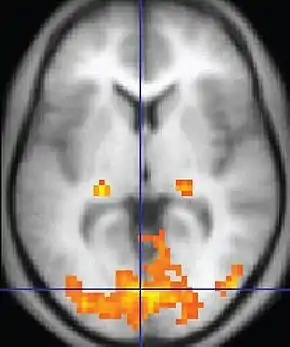

Diffusion weighted (DWI)ConventionalDWIMeasure of Brownian motion of water molecules.[26] High signal within minutes of cerebral infarction (pictured).[27]

Apparent diffusion coefficientADCReduced T2 weighting by taking multiple conventional DWI images with different DWI weighting, and the change corresponds to diffusion.[28] Low signal minutes after cerebral infarction (pictured).[29]

• In cerebral infarction, the infarcted core and the penumbra have decreased perfusion and delayed contrast arrival (pictured).[33]